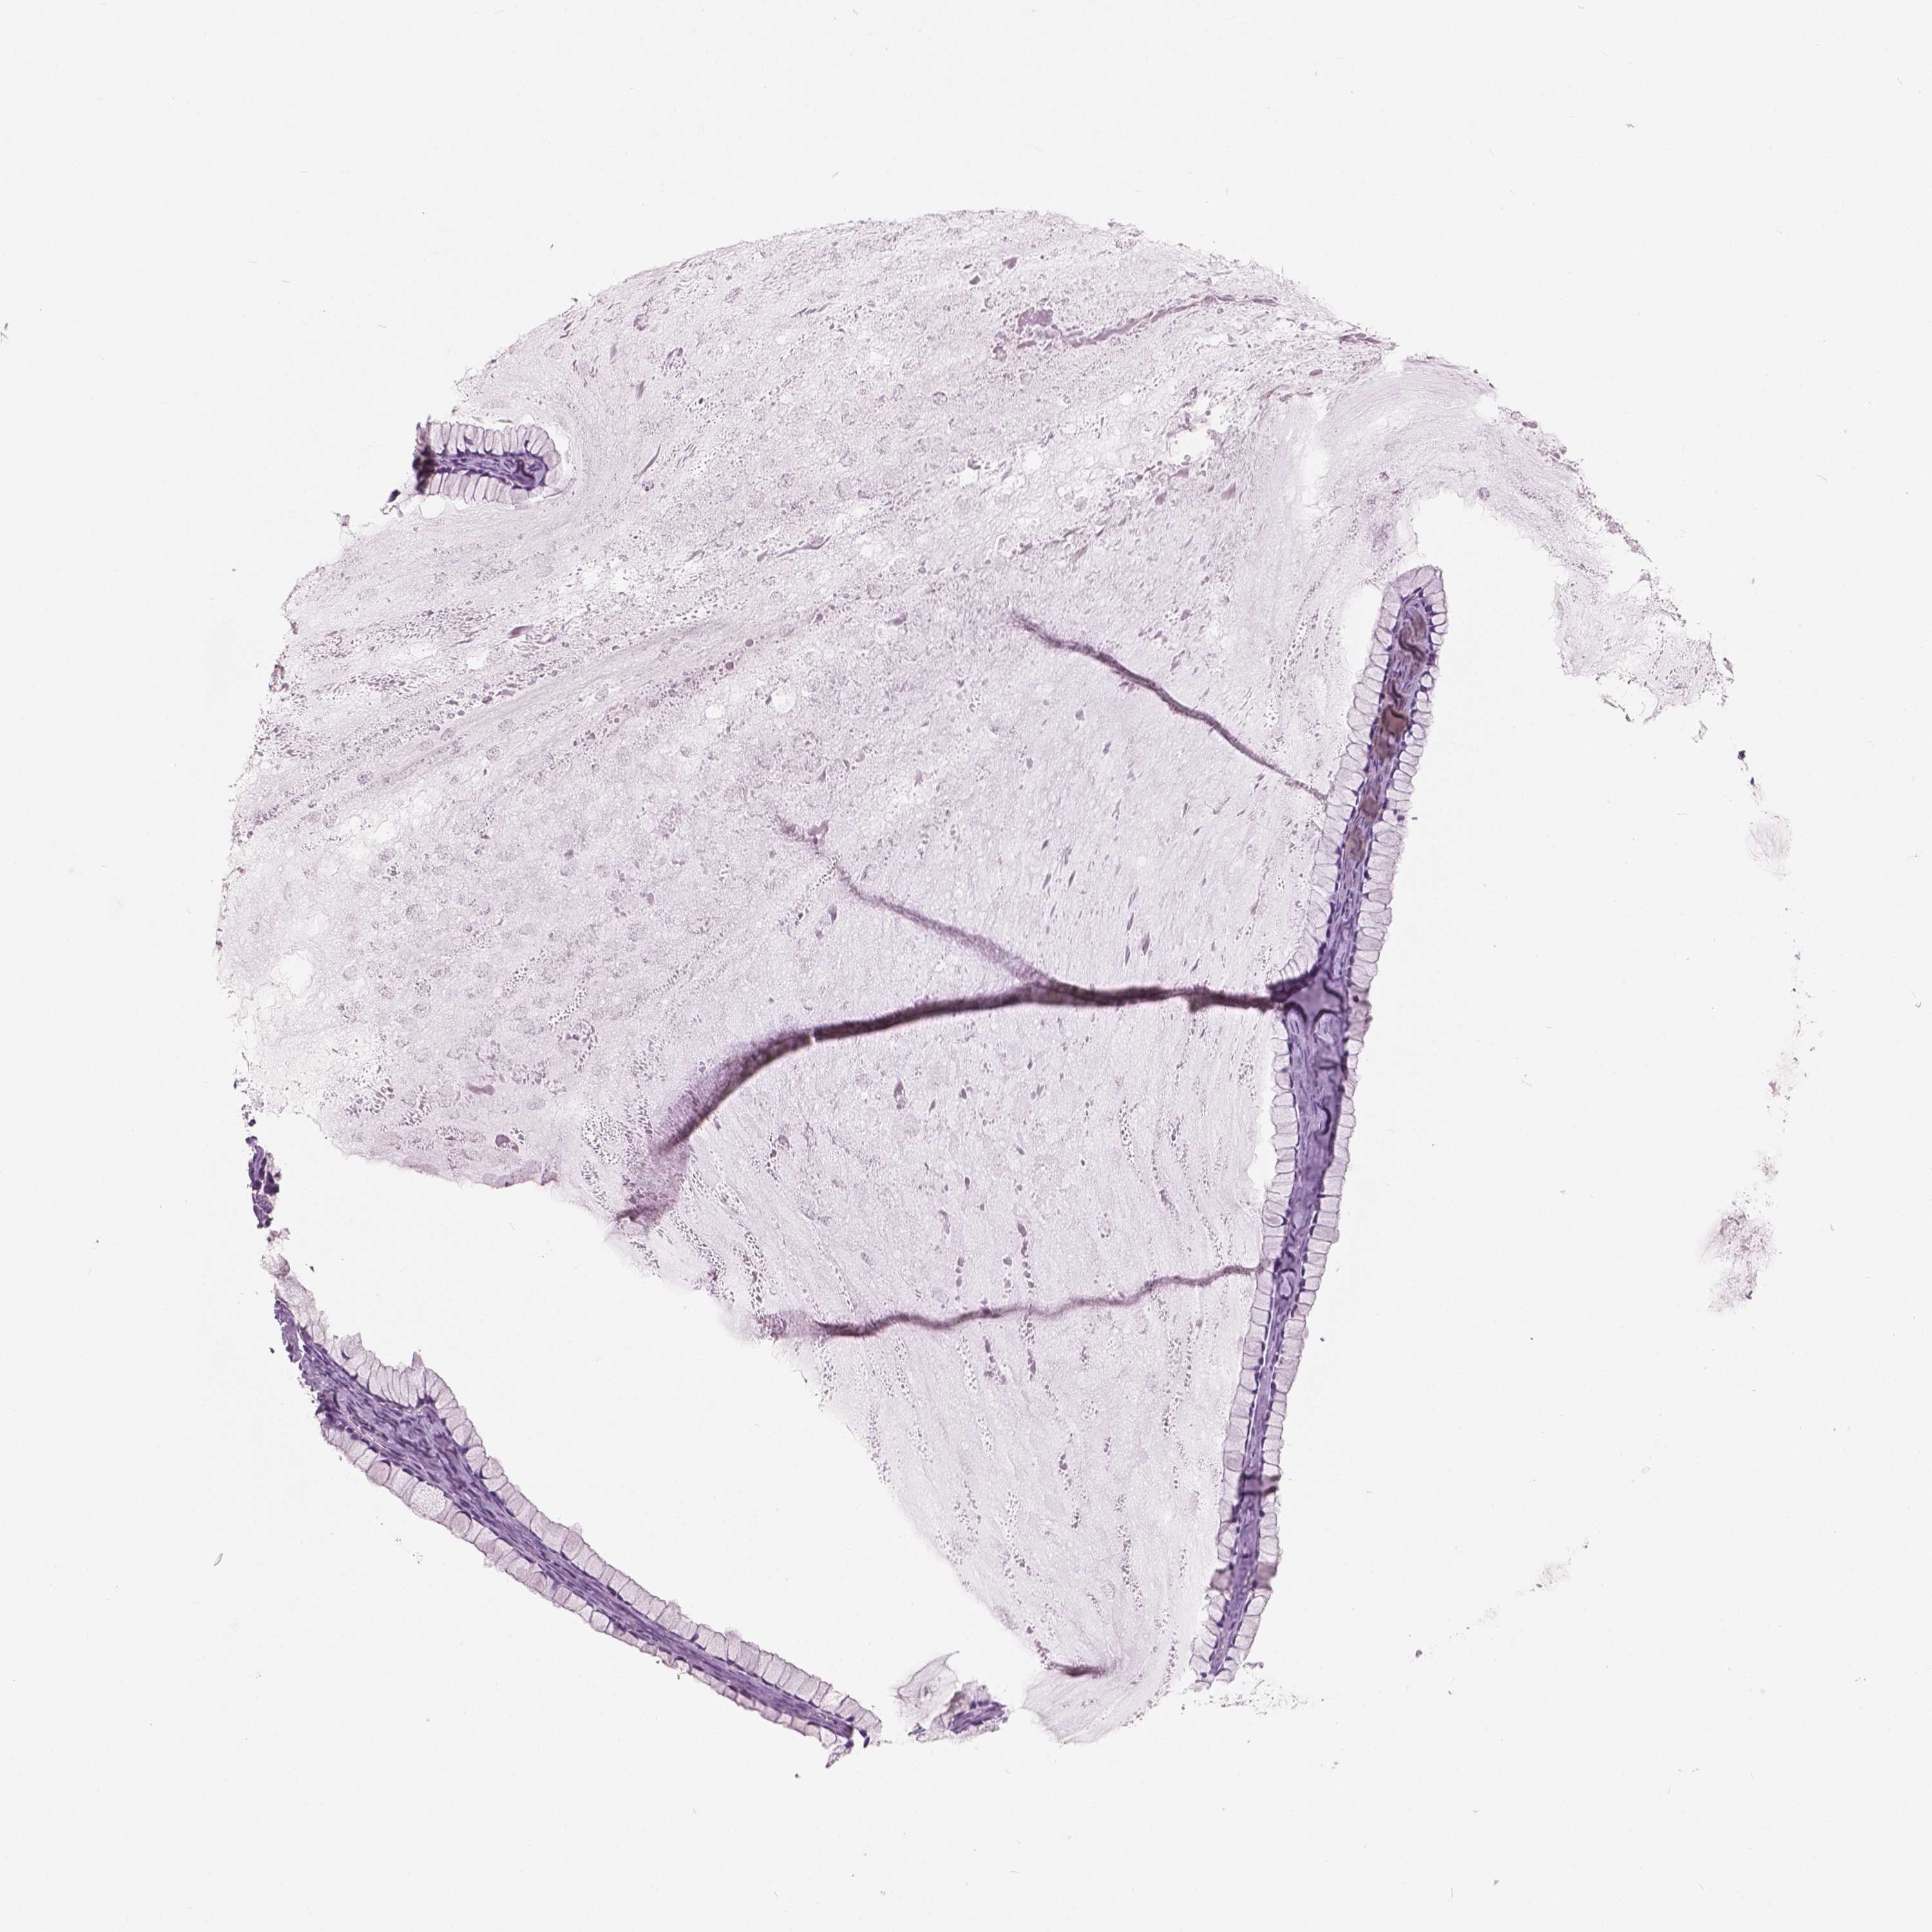

OVARIAN CANCER - Protein expressioni

A mouse-over function shows sample information and annotation data. Click on an image to view it in a full screen mode. Samples can be filtered based on level of antibody staining by selecting one or several of the following categories: high, medium, low and not detected. The assay and annotation is described here.

Note that samples used for immunohistochemistry by the Human Protein Atlas do not correspond to samples in the TCGA dataset.

Antibody stainingi

Antibody staining in the annotated cell types in the current human tissue is reported as not detected, low, medium, or high, based on conventional immunohistochemistry profiling in selected tissues. This score is based on the combination of the staining intensity and fraction of stained cells.

Each image is clickable and will lead to virtual microscopy that enables deeper exploration of all samples and also displays staining intensity scores, fraction scores and subcellular localization as well as patient and tissue information for each sample.

Antibody HPA035472

Antibody HPA035473

Antibody HPA064835

Cystadenocarcinoma, serous, NOS

Cystadenocarcinoma, mucinous, NOS

Carcinoma, endometroid